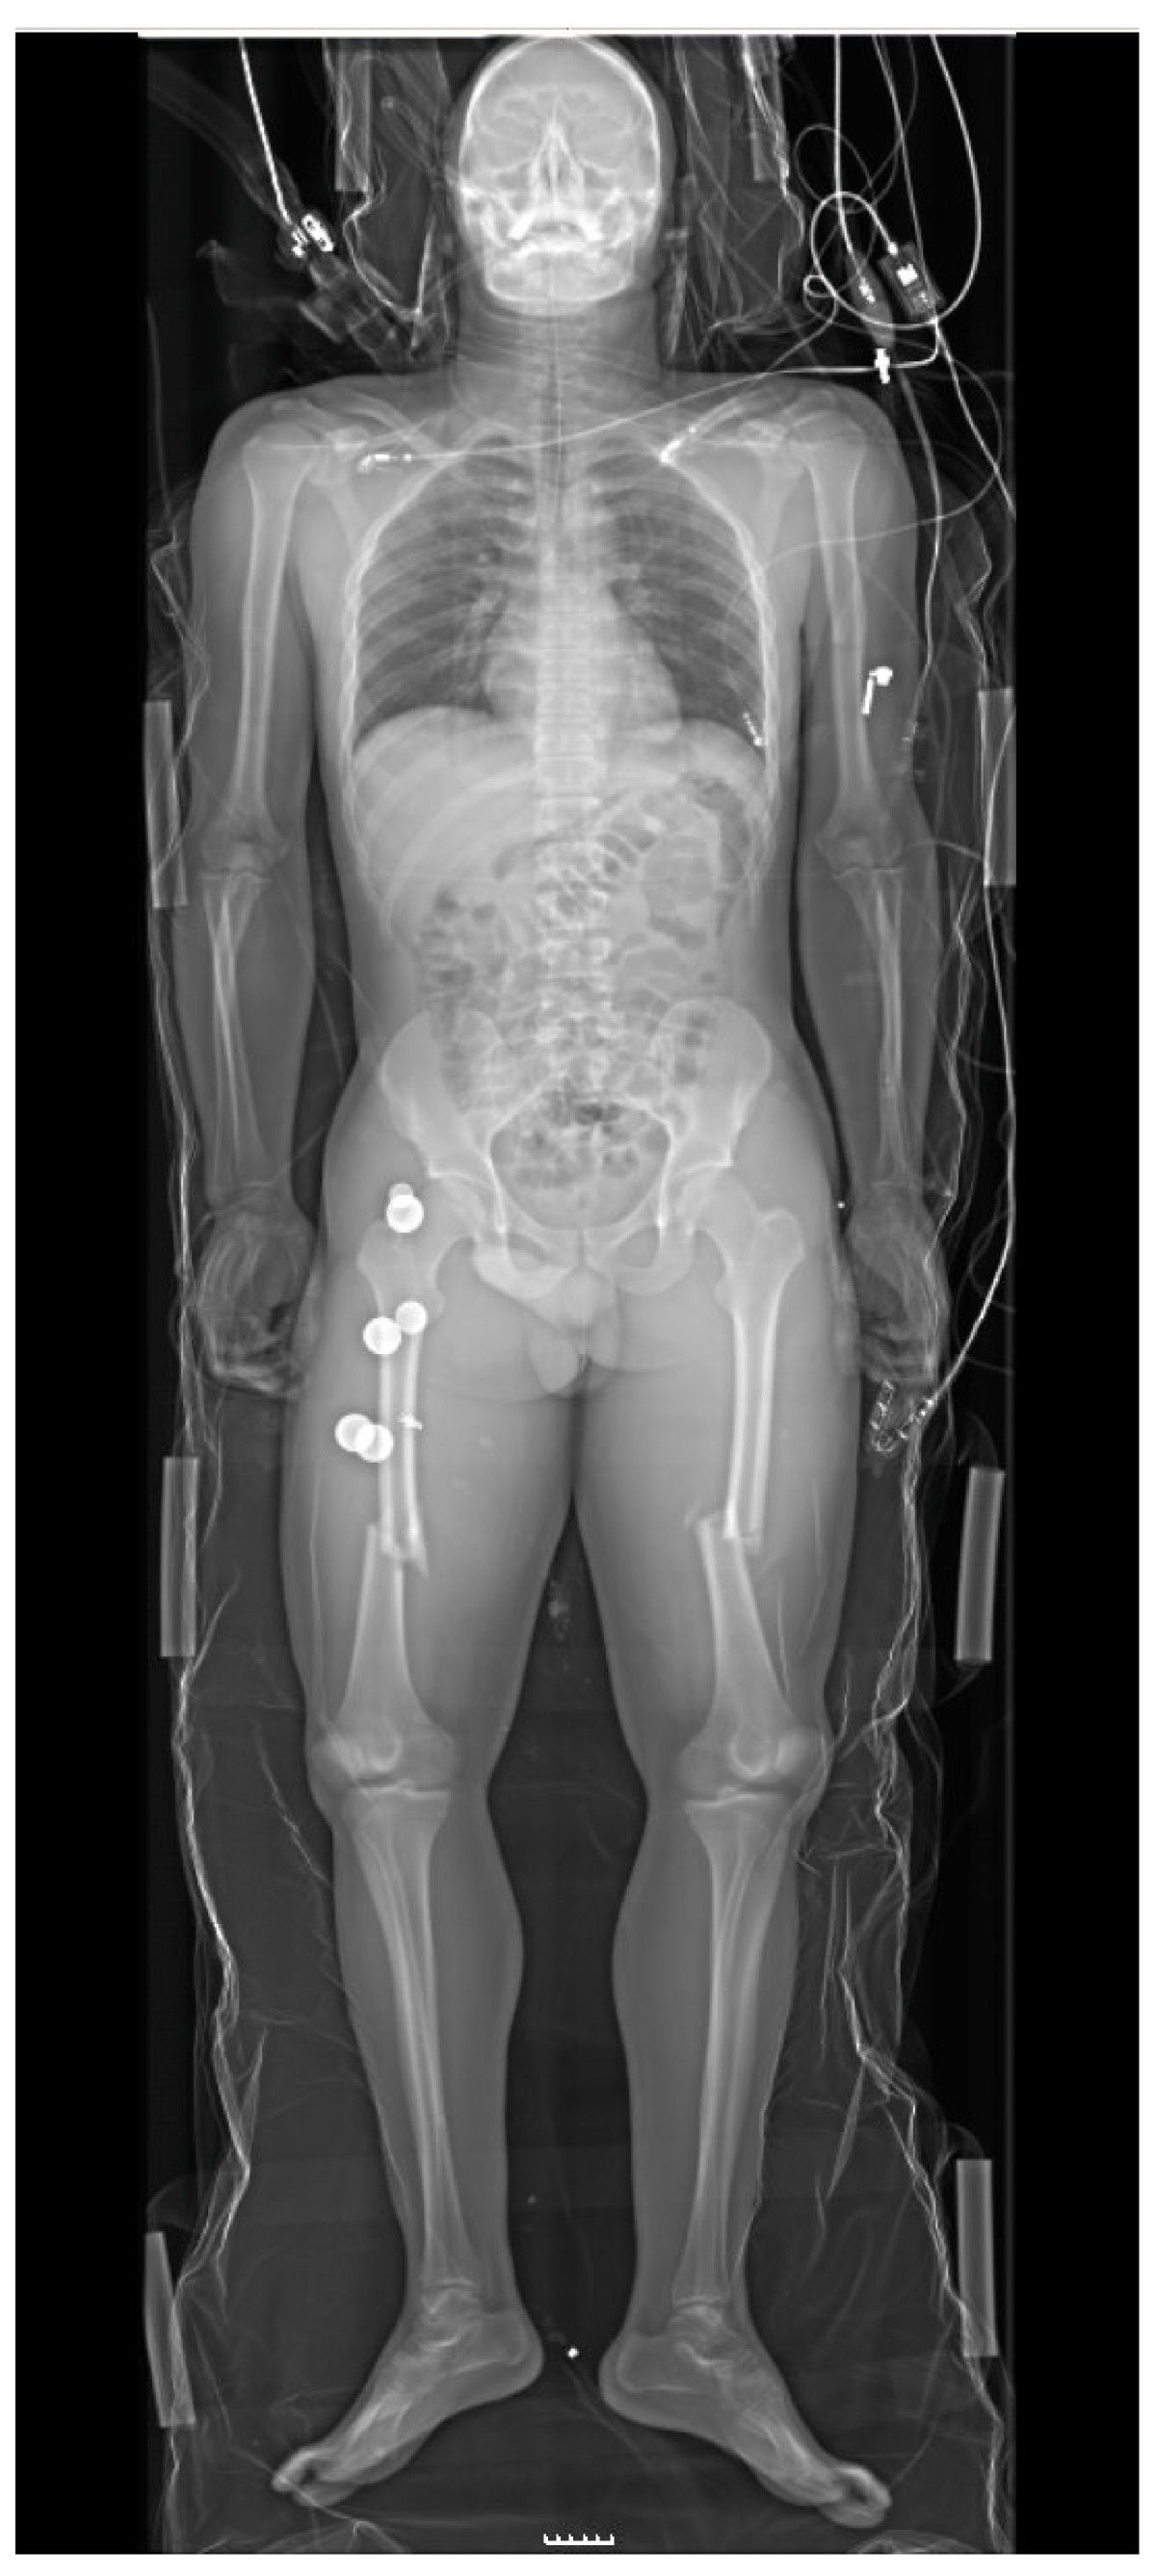

주요 외상을 입은 환자는 일반적으로 흉부 및 골반 방사선 촬영을 받으며,[40] 부상 기전과 증상에 따라 내출혈 여부를 확인하기 위해 외상 환자 초음파 검사 (FAST)를 받는다. 비교적 안정적인 혈압, 심박수, 충분한 산소 공급을 보이는 환자의 경우, CT 스캔이 유용하다.[40][26] 전신 스캔이라고도 하는 전신 CT 스캔은 심각한 외상을 입은 환자의 생존율을 향상시킨다.[23][24] 이러한 스캔은 방사선 조영제를 정맥 주사로 사용하며, 경구 투여는 하지 않는다.[25] 외상 상황에서 적절한 신장 기능을 확인하지 않고 정맥 조영제를 투여하면 신장에 손상을 줄 수 있다는 우려가 있지만, 이는 심각한 문제로 보이지는 않는다.[26]

양쪽 대퇴골(허벅지 뼈) 골절이 뚜렷하게 나타나는 외상 부위의 전신 방사선 사진으로, 심각한 외상을 나타냄